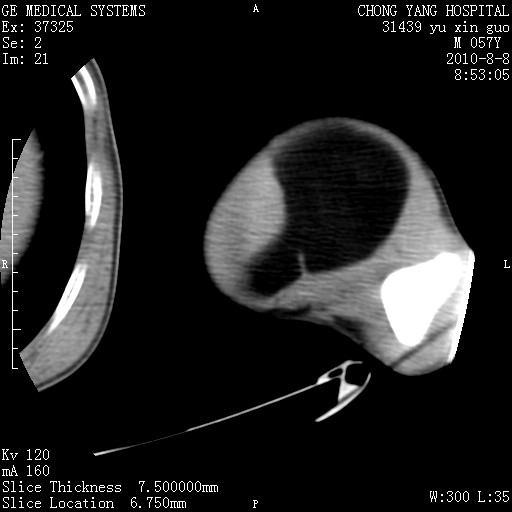

标题: CT28267:M57Y 上臂包块8年余。 [打印本页]

标题: CT28267:M57Y 上臂包块8年余。

包膜光滑、完整的脂肪密度肿块,支持脂肪瘤。

上臂软组织内脂肪瘤。